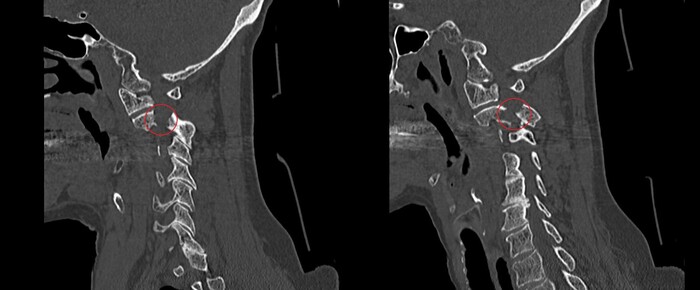

Итак, на КТ шейного отдела позвоночника, а именно на боковых (сагиттальных) реконструкциях бросалось в глаза смещение вперёд тела 2го шейного позвонка относительно третьего шейного позвонка с т.н. "ступенькой":

Причиной этого могут быть как дегенеративные изменения (артроз) межпозвоночных суставов, так и травматические повреждения с возникшей нестабильностью. Второе как-раз и обнаружилось на поперечных (аксиальных) реконструкциях, где определялся двустронний перелом ножек второго шейного позвонка:

Который лучше всего был виден на боковых (сагиттальных) срезах: